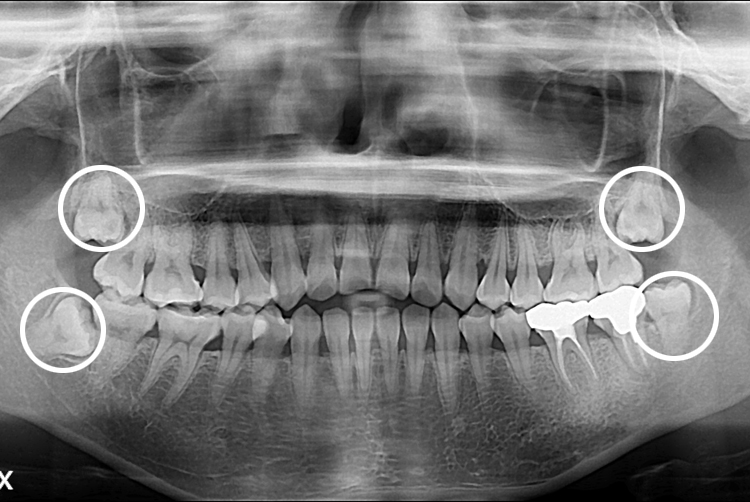

[사랑니] 완전매복 사랑니 발치

치료전 : 2016-06-17

세종치과는 구강악안면외과학 박사이신 원장님이 발치하는 치과입니다.